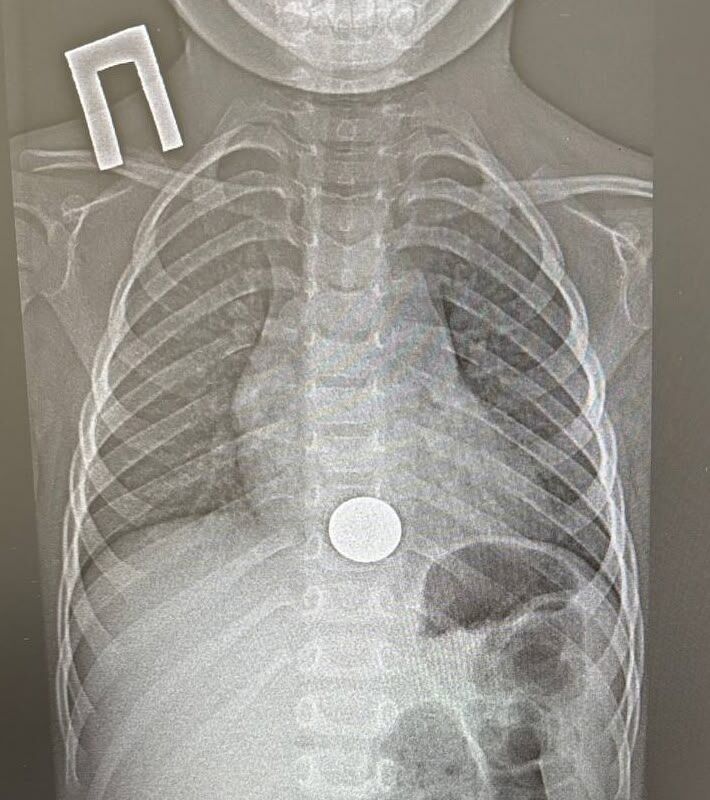

Двухлетний ребенок проглотил монету и попал в больницу в Татарстане

В Татарстане спасли двухлетнего ребенка, проглотившего монету

В Татарстане ребенок проглотил монету и попал в больницу. Об этом сообщает пресс-служба ГАУЗ НДРБ с ПЦ.

Инцидент произошел 15 декабря. Малолетний взял у старшего брата монету, чтобы поиграть с ней, и случайно ее проглотил. Ребенок сразу рассказал об этом родителям, и мать оперативно доставила его в больницу. Мальчик жаловался на боль за грудиной.

Пациенту провели рентген и обнаружили у него инородное тело в пищеводе, детский врач выполнил эндоскопическое удаление монетки. Вся процедура заняла около минуты.